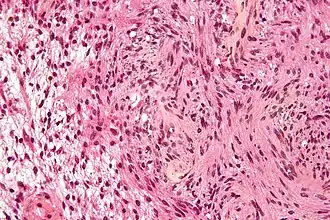

| Micrografia de um schwannoma com área Antoni A (centro e direita) e área Antoni B (esquerda). Tinção HPS. | |